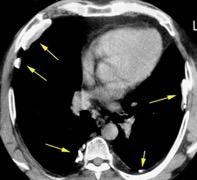

> Grasa Extrapleural (60-80%)

Forma lenticular o elíptica Ángulos obtusos

Nivel hidroaéreo o burbujas

Hallifax RJ et al. State-of-the-art: Radiological investigation of pleural disease Respiratory Medicine 2017

Engrosamiento de la pleura parietal 36/ 59 exudados (61%) 56% de D. paraneumónicos 100% de empiemas Especificidad.. 96%.

Signo de la Pleura separada “Split pleural sign”

Capas pleurales de grosor uniforme realzadas por el contraste

No específico de empiema. Indica “exudado”. 68% de pacientes con empiema pleural.

Capas pleurales de grosor uniforme

Realce grasa extrapleural (30%)

> Grasa Extrapleural. (60-80%)

Kraus GJ. Split pleural sign. Radiology 2007